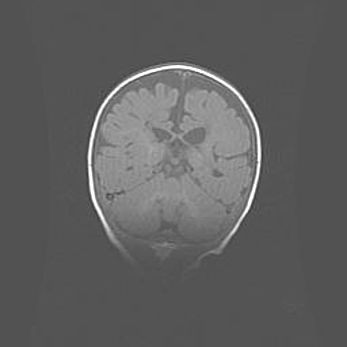

Наружная гидроцефалия с возможной атрофией височных областей.

Возраст: 28 дней

Вес: 3670 г

Пол: мужской

Окружность головы: 38 см

Срок гестации: 40 недель

Гидроцефалия головного мозга у новорожденных – это заболевание, которое характеризуется скоплением избыточного количества спинномозговой жидкости в желудочковой системе головного мозга в результате затруднения её перемещения от места выработки к месту поглощения в кровеносную систему или вследствие нарушения абсорбции. При открытой наружной форме гидроцефалии у новорожденных расширяются и переполняются субарахноидные пространства.

При нормотензивных  формах,  которые,  как  правило,  являются  следствием  перенесенных ишемических  повреждений  паренхимы  мозга,  возможно  сочетание микроцефалии  с нормотензивной гидроцефалией. В основе данных изменений лежит атрофия больших полушарий с преимущественной  локализацией  в  лобно-височных  областях.